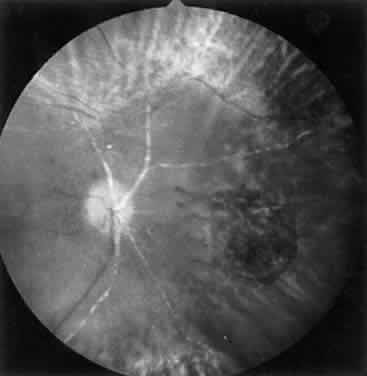

Intravenous fluorescein angiography may be helpful in delineating the extent of infection and elucidating the cause of central visual loss. In the early frames, choroidal perfusion defects may be seen; these defects are caused by areas of focal choroidal inflammatory cell accumulation and overlying retinal pigment epithelial damage (Fig. 16). Such choroidal perfusion defects may occur away from zones of active necrosis.42 Acute obstruction of the central retinal artery or any of its branches may be present. Peripheral views in the areas of active retinitis commonly show little or no intravascular fluorescein in the retinal arteries and veins. Often an abrupt “cut-off” of the intravascular fluorescein may be apparent at the edges of the retinal inflammation (see Fig. 4B and C). Areas of active retinitis show blockage of the underlying choroidal fluorescein pattern (see Fig. 7B). Recirculation phase views may reveal macular leakage, optic disc, and retinal vasculature staining.

Culbertson and coworkers recommended that confluent laser photocoagulation be applied posterior to the active retinitis in all cases of ARN.14 This treatment creates a “new” ora serrata within the healthy retina in order to localize to the periphery any subsequent retinal detachment. Laser treatment does not stop the progression of retinitis, and therefore repeat treatments may be necessary. Because clear media is required to perform laser treatment successfully, the cases manifesting the greatest vitreous reaction are least likely to be suitable for laser photocoagulation. Sternberg and associates noted retinal detachment in 17% of eyes treated prophylactically with laser compared with 67% of untreated eyes.12 Han and colleagues reported on five eyes with ARN that received laser treatment in which the retina did not subsequently detach.63 Most clinicians currently perform prophylactic laser photocoagulation circumferentially for 360 degrees at the junction of necrotic and healthy retina at the time of diagnosis of ARN if visualization is adequate (Fig. 17).